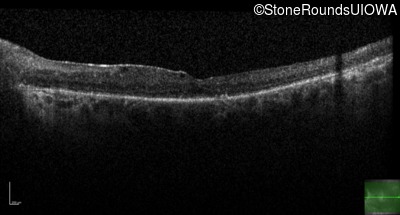

Age at visit: 25 years

Age at visit: 26 years